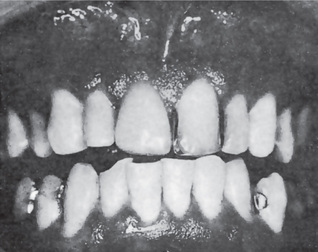

Figure 19-5 Oral lichen planus.

(A) Note the basilar degeneration and band-like infiltration of inflammatory cells in the subepithelial zone. (B) Histopathology of lichenoid mucositis (H and E x 100). Note the diffuse infiltration of inflammatory cells involving parts of submucosa. (C) Photomicrograph of Langerhans cells in lichen planus (Gold Chloride staining x400). (D) Photomicrograph of Langerhans cells in lichenoid mucositis (Gold Chloride staining x400) Courtesy of the Dept of Oral Pathology, Ragas Dental College and Hospital, Chennai.

Histopathologic examination of lesional tissue is the most relevant investigation in cases of OLP. Typical findings include hyperparakeratosis or hyperorthokeratosis with thickening of the granular layer, acanthosis with intracellular edema of the spinous cells in some instances, the development of a ‘saw tooth’ appearance of the rete pegs. Band-like subepithelial mononuclear infiltrate consisting of T-cells and histiocytes; increased numbers of intraepithelial T-cells; and degenerating basal keratinocytes that form colloid (Civatte, hyaline, cytoid) bodies, which appear as homogenous eosinophilic globules are consistently seen.

Degeneration of the basal keratinocytes and disruption of the anchoring elements of the epithelial basement membrane and basal keratinocytes (e.g. hemidesmosomes, filaments, fibrils) weakens the epithelial-connective tissue interface. As a result, histologic clefts (i.e. Max-Joseph spaces) may form, and blisters on the oral mucosa (bullous lichen planus) may be seen at clinical examination. B cells and plasma cells are uncommon findings (Fig. 19-5).